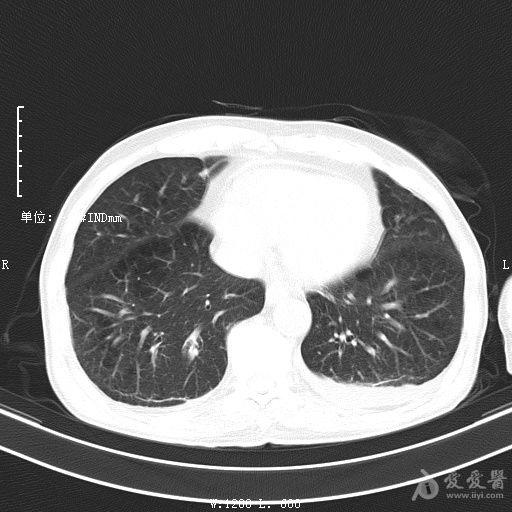

最新的肺炎疫情形势严峻,病毒变异使得防控工作更加复杂,许多地方出现了新的病例,甚至有些地区的疫情出现了反弹,这不仅是对医疗系统的考验,更是对每一个生命的考验,我们需要密切关注疫情动态,共同应对这场挑战。💪